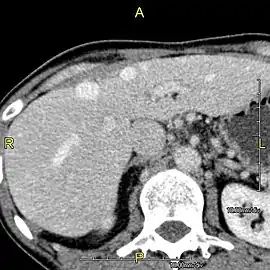

A CT scan in which the liver and portal vein are shown

With the recent advances of noninvasive imaging, living liver donors usually have to undergo imaging examinations for liver anatomy to decide if the anatomy is feasible for donation. The evaluation is usually performed by multidetector row computed tomography (MDCT) and magnetic resonance imaging (MRI). MDCT is good in vascular anatomy and volumetry. MRI is used for biliary tree anatomy. Donors with very unusual vascular anatomy, which makes them unsuitable for donation, could be screened out to avoid unnecessary operations.

Phase contrast CT image. Contrast is perfusing the right liver but not the left due to a left portal vein thrombus.